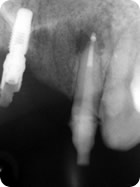

Retratamento Endodôntico

Retratamento Endodôntico 1

Retratamento Endodôntico 2

Retratamento Endodôntico 3

Retratamento Endodôntico 4